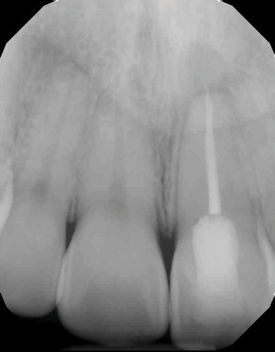

(3.) Preoperative radiograph of asymptomatic carious exposures on teeth Nos. 12 and 13.

Figure 3

(4.) Postoperative radiograph of teeth Nos. 12 and 13 following treatment with direct pulp caps using a bioceramic dentin substitute material.

Figure 4